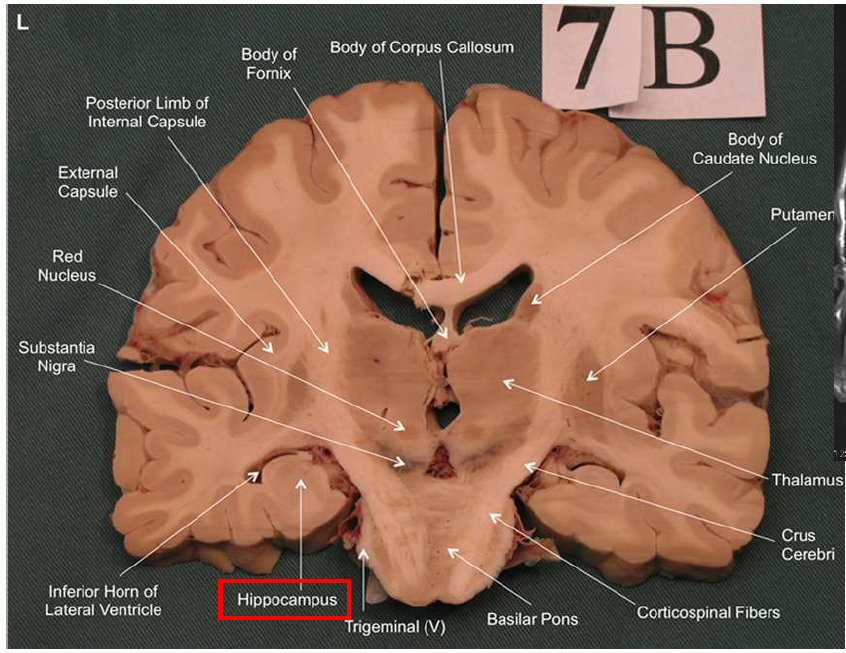

What structure has the function of reducing unpleasant effects of stress, psychological resistance, and formation of new memories?

hippocampus

What is the fornix of the hippocampus?

Hippocampus output pathway (C-shaped)

Connects hippocampus to hypothalamus/mamillary bodies

Carries information to and from hippocampus

Important for memory consolidation and retrieval

What is this?

hippocampal fornix

How does the hippocampus form memories?

Association areas activate the hippocampus, which reverberates in the Papez circuit until information is stored permanently

Hippocampus → fornix → mamillary bodies → anterior thalamic nucleus → cingulate cortex → hypothalamus

What is Korsakoff syndrome?

Memory disorder from thiamine (vitamin B1) deficiency. Often linked to chronic alcoholism.

Symptoms: anterograde amnesia (can't form new memories), confabulation (making up memories), disorientation, apathy.